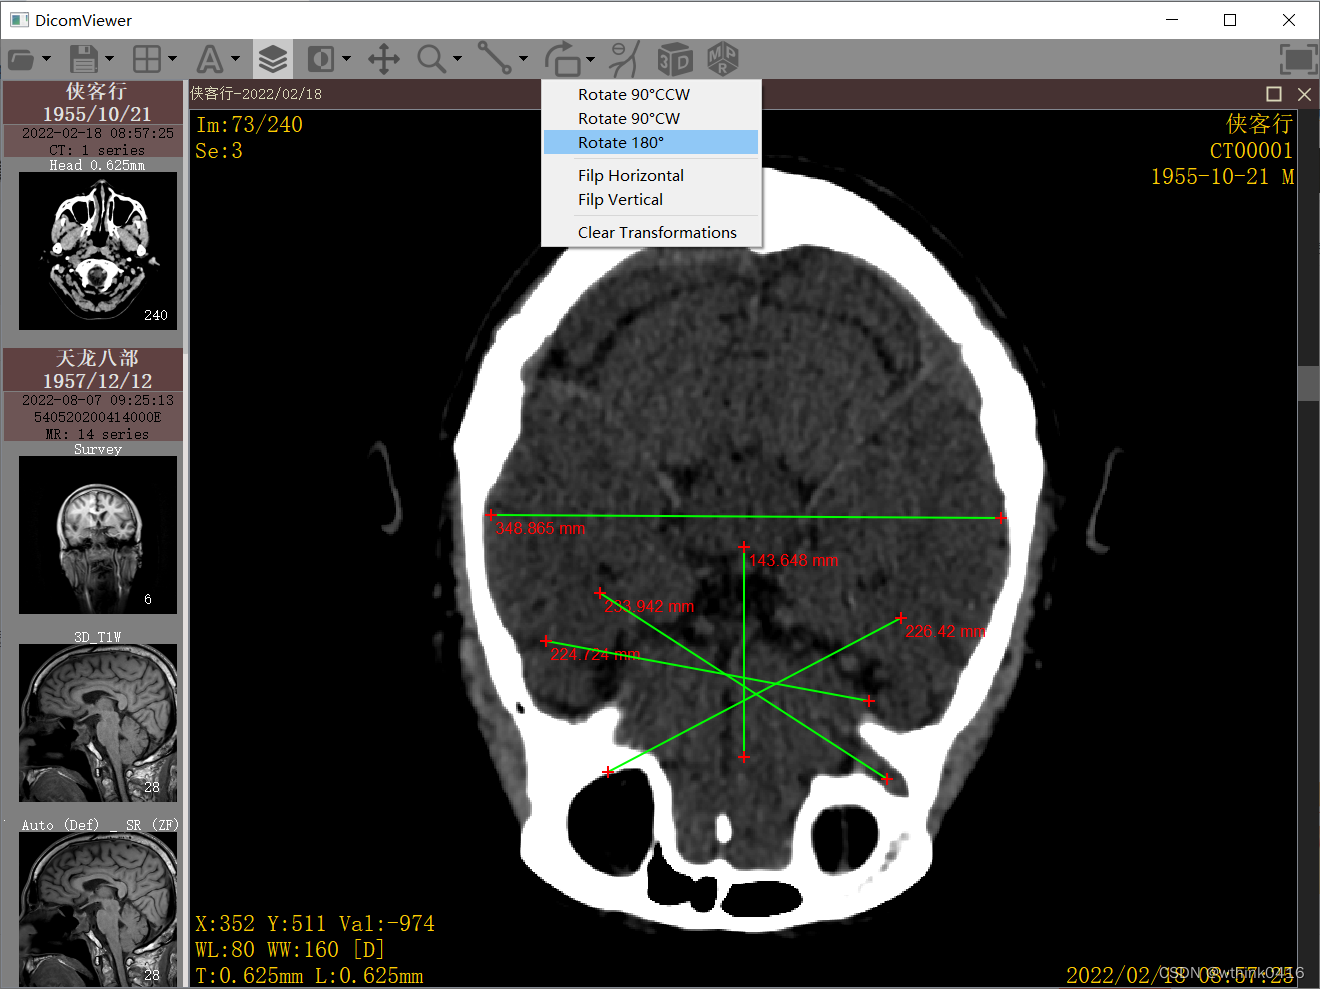

9、点击![]() 旋转图标后,可以实现图像顺时针旋转90°,下拉菜单支持预设一些旋转度数

旋转图标后,可以实现图像顺时针旋转90°,下拉菜单支持预设一些旋转度数